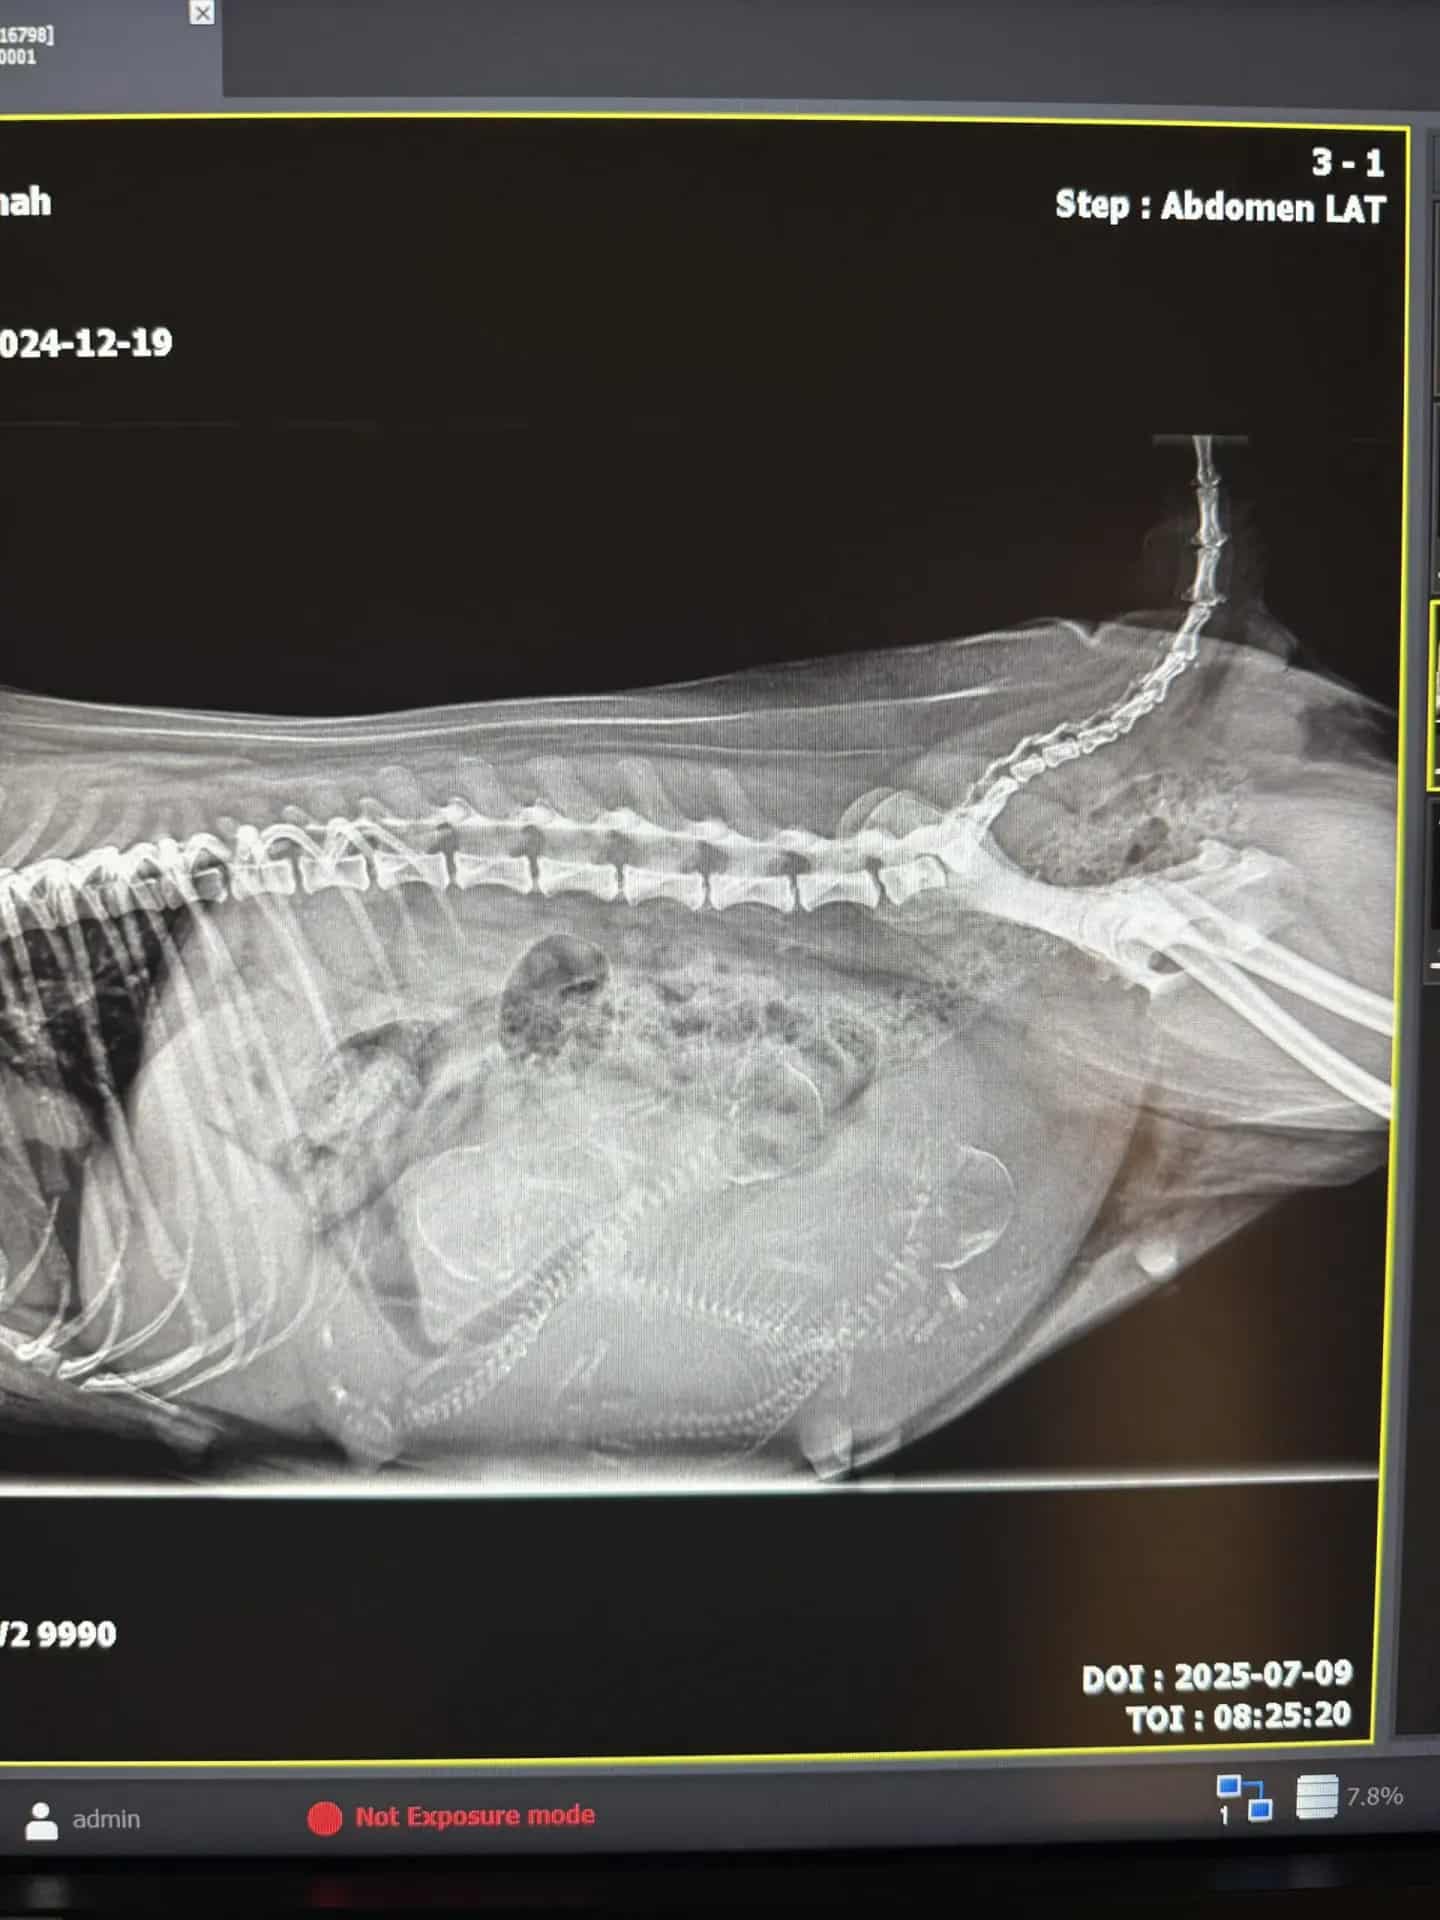

Savannah väntar 3st valpar här i början av vecka 30